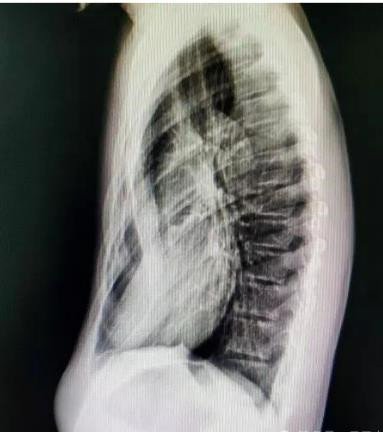

癥狀:胸骨及兩側(cè)肋骨向內(nèi)凹陷,形成 “漏斗狀” 畸形,幼兒期可能癥狀較輕,青春期隨著身高快速增長,凹陷會(huì)逐漸加深,嚴(yán)重時(shí)胸骨可貼近脊柱。

若發(fā)現(xiàn)孩子胸口有凹陷,及時(shí)帶娃到胸外科就診,通過胸部 X 線、CT 掃描、肺功能測試、心臟超聲等檢查,明確凹陷程度和心肺受壓情況,避免延誤干預(yù)時(shí)機(jī)。